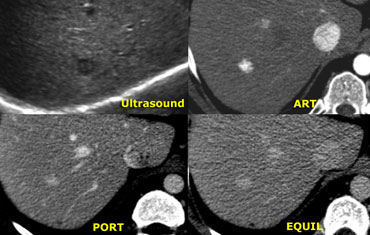

Adenoma: non-specific features on CT Adenoma: non-specific features on CT

Adenoma (3)

On the left an US image of an incidentally found lesion in a 50 y old female.

Work up was done with CT, but only non-specific features were found without signs of hypervascularity. .

Continue with next images.

Adenoma: capillary blush in arterial phase and signal loss in out of phase image indicating the presence of fat. Adenoma: capillary blush in arterial phase and signal loss in out of phase image indicating the presence of fat.

In contrast to the CT, there clearly is enhancement in the arterial phase on MR, again demonstrating that MR depicts enhancement better than CT.

The enhancement is due to a capillary blush, most intense in the arterial phase with apparent wash-out in portal and equilibrium phase, due to greater enhancement of the surrounding parenchyma.

In the 'out of phase' image there is signal loss indicating that the lesion contains fat, which is very suggestive for adenoma.

A HCC may also contain fat, but in this case there is no cirrhosis and the entire lesion shows signal loss, which we would not expect in HCC.